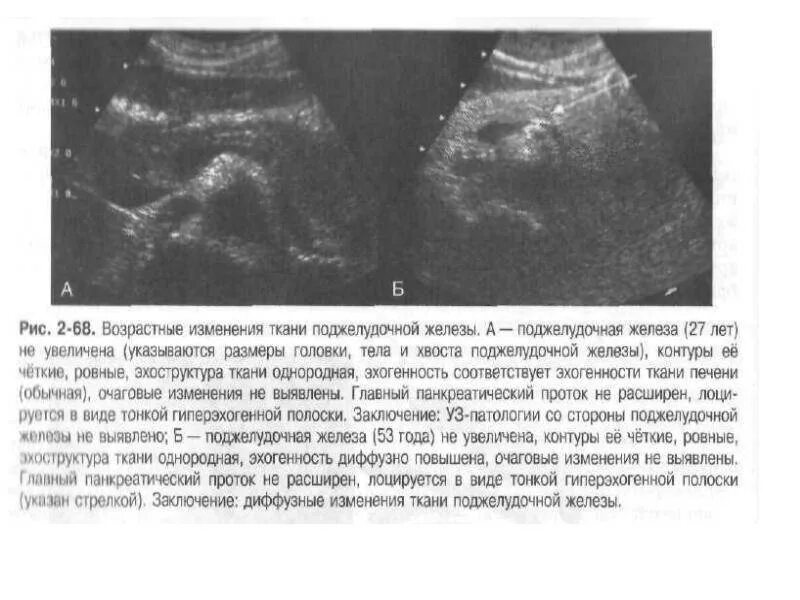

Диффузные изменения простыми словами